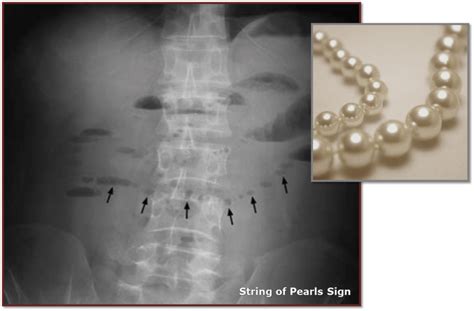

Timothy Samons Blog